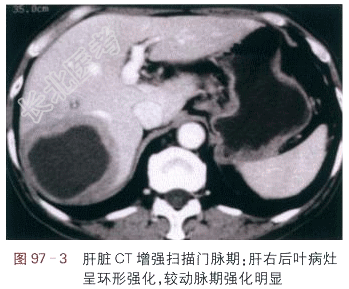

读片分析:肝右后叶包膜下见一低密度团块,呈囊性,内部密度均匀,见一略低密度囊壁,病灶边缘模糊(见图97-1),肝脏CT增强扫描:肝右后叶病灶囊壁呈环形强化,表现为“靶征”,病灶中央为低密度,周边见强化环,环周边为低密度区,病灶边缘模糊(见图97-2~图97-3)。